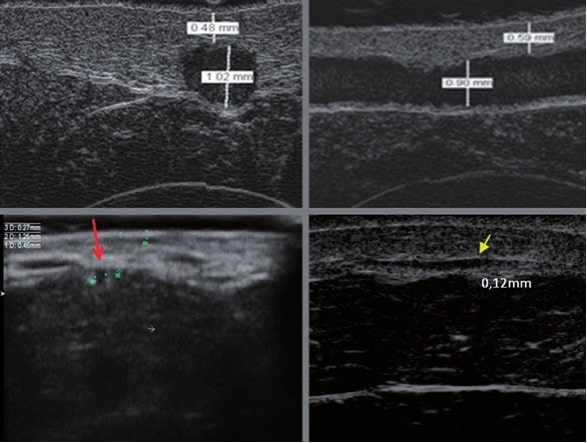

La ecografía Doppler permite obtener imágenes de grandes vasos y perforantes que suelen estar situados en las capas más profundas del tejido subcutáneo (fig. 1). Desgraciadamente, la ecografía convencional no es capaz de obtener imágenes de vasos más pequeños. Para visualizar los vasos más pequeños situados cerca de la superficie de la epidermis y en la capa superior del tejido subcutáneo, se utiliza el HFU (fig. 1). Gracias al uso de transductores con frecuencias superiores a 20 MHz, se obtiene una imagen ecográfica de alta resolución en la que podemos diferenciar estructuras menores de 0,1 mm. Sin embargo, cuanto mayor es la resolución, menor es la penetración del haz de ultrasonidos en las capas de la piel. Por lo tanto, dependiendo del transductor y del aparato, es posible penetrar en la piel hasta una profundidad de 20-30 mm como máximo. Tal penetración, junto con la alta resolución de la imagen, permite la evaluación incluso de vasos sanguíneos muy pequeños (fig. 2). Durante el examen con el uso de transductores de alta frecuencia, se puede evaluar con precisión el curso y la ubicación de los pequeños vasos en la piel. Esto es particularmente relevante para la selección del método de cierre del vaso y la planificación del procedimiento ya que, en la práctica, la superficie de la piel muestra muy a menudo únicamente un pequeño número de vasos o un ligero fragmento de un vaso; solo tras el examen por ecografía podemos determinar su número y curso reales. Para un cierre eficaz del vaso, es necesario hacerlo en toda su longitud. No debe limitarse al fragmento visto «a simple vista» en la superficie de la piel, ya que el cierre del fragmento causará su rápida recanalización(7). Con frecuencia, el vaso visible en la superficie de la piel cambia su curso, se vuelve más tortuoso y se desplaza a las capas más profundas de la piel(8). Por lo tanto, el curso de la vena y las perforantes deben conocerse y determinarse bien antes del procedimiento. El HFU también permite obtener imágenes de las perforantes entre pequeños vasos. Además, aparte de la evaluación del curso y la anatomía, la imagen ecográfica, gracias al software de ultrasonidos, también permite determinar los parámetros básicos como el diámetro del vaso, el grosor de su pared, la profundidad en la piel así como la presencia o ausencia de perfusión en el interior del vaso(6) (fig. 3). Gracias al transductor electrónico multielemento con la frecuencia de 40 MHz introducido en el mercado por Ultrasonix, también es posible visualizar la perfusión en los vasos en el modo Doppler color (fig. 4).